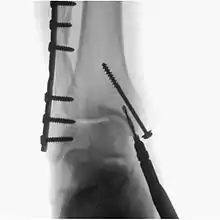

Surgical fluoroscopy

Fluroscopy is used during various surgeries like Orthopaedic surgery, Podiatric surgery etc. In Podiatric surgerries and Orthopaedic surgeries it is used to guide fracture reduction and in use in certain procedures that have extensive hardware.[5]